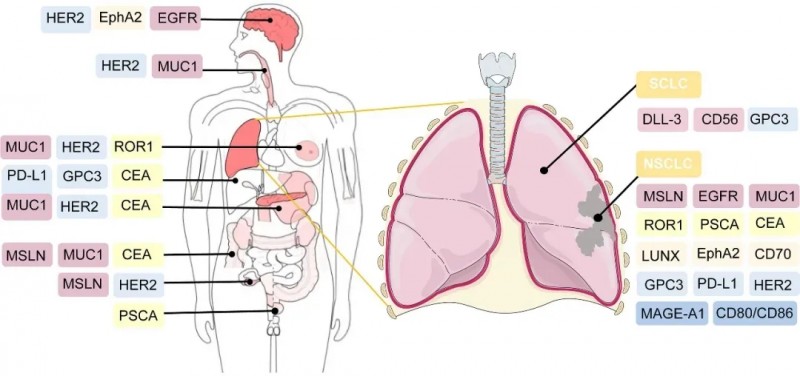

▼临床前和临床试验中,CAR-T细胞疗法的潜在靶向抗原

▲图源“frontiers”,版权归原作者所有,如无意中侵犯了知识产权,请联系我们删除

好消息是,目前有多款CAR-T临床实验正在火热招募中,主要针对Claudin18.2、GPC3、GUCY2C、PSMA、CEA、间皮素(mesothelin)、MUC-1、BCMA、CD1、CD20等靶点。以及胰腺癌、胃癌、肝癌、结直肠癌、神经胶质瘤、肺癌、多发性骨髓瘤、多发性骨髓瘤、弥漫大B细胞淋巴瘤等癌种。